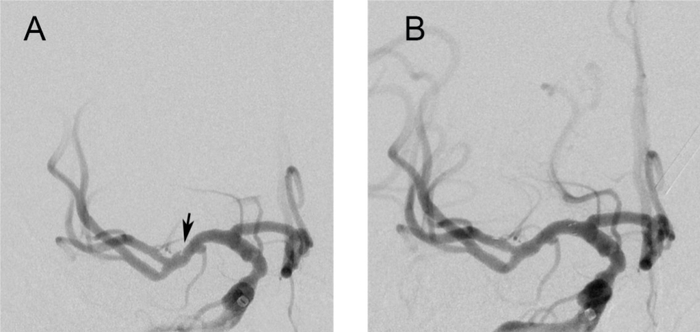

诊断基本清楚了,接下来治疗怎么办?患者3年的时间反复发作服用了很多药物无效,团队讨论后决定跟家属沟通血管内介入治疗的尝试选择,患者及家属慎重考虑后同意介入治疗,2023年5月25日进行了右侧大脑中动脉支架植入术(图3),截至目前患者之前症状未再发作,收到了很好的治疗效果。

图3. A支架置入术前可见右侧大脑中动脉管腔内充盈缺损;支架置入术后右侧大脑中动脉管腔内充盈缺损消失基于该患者的特殊就诊经历与特征性的影像学改变,西南医院神经内科团队首次提出了大脑中动脉蹼的概念并近期在医学顶刊子刊JAMA Neurology上发表(IF 29分)。隐源性卒中的发病机制依然复杂,需要我们不断探索。7.0T核磁共振成像分辨率更高、具备更好的脑脊液抑制效果,有助于识别颅内复杂疑难病变。西南医院拥有西南地区唯一一台MAGNETOM Terra 7T人体磁共振机,可以更好地为颅脑病变的诊治与研究提供强有力的支撑,目前已经开展系列研究。